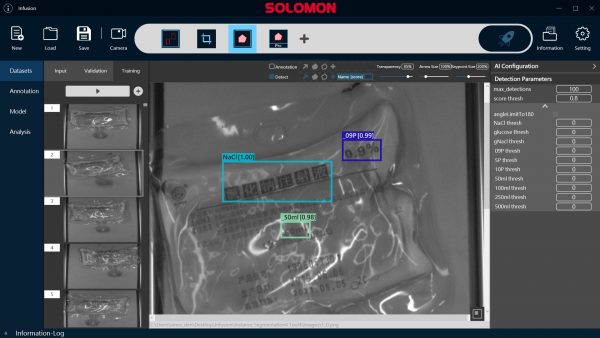

AI-Powered Feature Recognition

With SolVision‘s segmentation tool, various labels can be identified from sample images to train a visual inspection system capable of classifying information on IV bags based on their distinctive features. SolVision’s advanced AI-based technology is also unaffected by transparent objects, label complexity, or appearance.